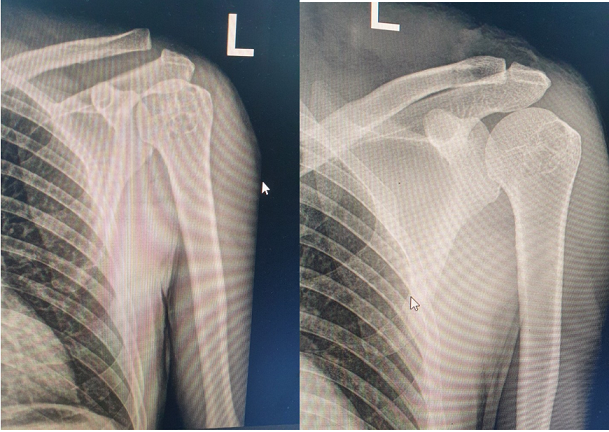

Kết quả kiểm tra phim chụp X-quang khớp vai trái sau phẫu thuật cho thấy xương nắn vào khớp tốt. Sau phẫu thuật 4 ngày, tình hình sức khỏe của bệnh nhân ổn định và đã được ra viện vào ngày 24/3/2023.

Hình ảnh phim chụp X-quang của bệnh nhân trước và sau khi thực hiện phẫu thuật